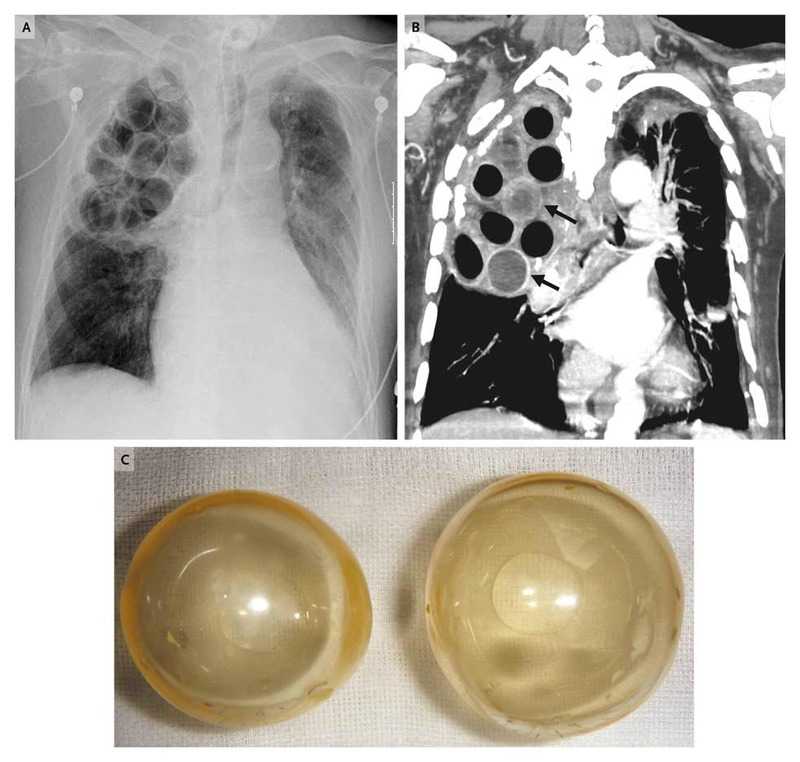

Autopsy revealed that the balls used in plombage (3 to 4 cm in diameter) had become imbedded in fibrous tissue, with pleural calcification and moderate inflammatory changes that were consistent with pneumonia and a history of successfully treated tuberculosis; there was no evidence of active tuberculosis.

Radiographic and computed tomographic (CT) images of the chest (Panels A and B, respectively) revealed the balls, most of which were lucent (Panel C) and some of which had broken inside the pleural space.

Muddy fluid was observed inside some of the balls, which was consistent with the high-density fluid seen inside the balls on the CT image (arrows in Panel B). Pseudomonas aeruginosa was cultured from both the fluid in the balls and the patient’s blood.